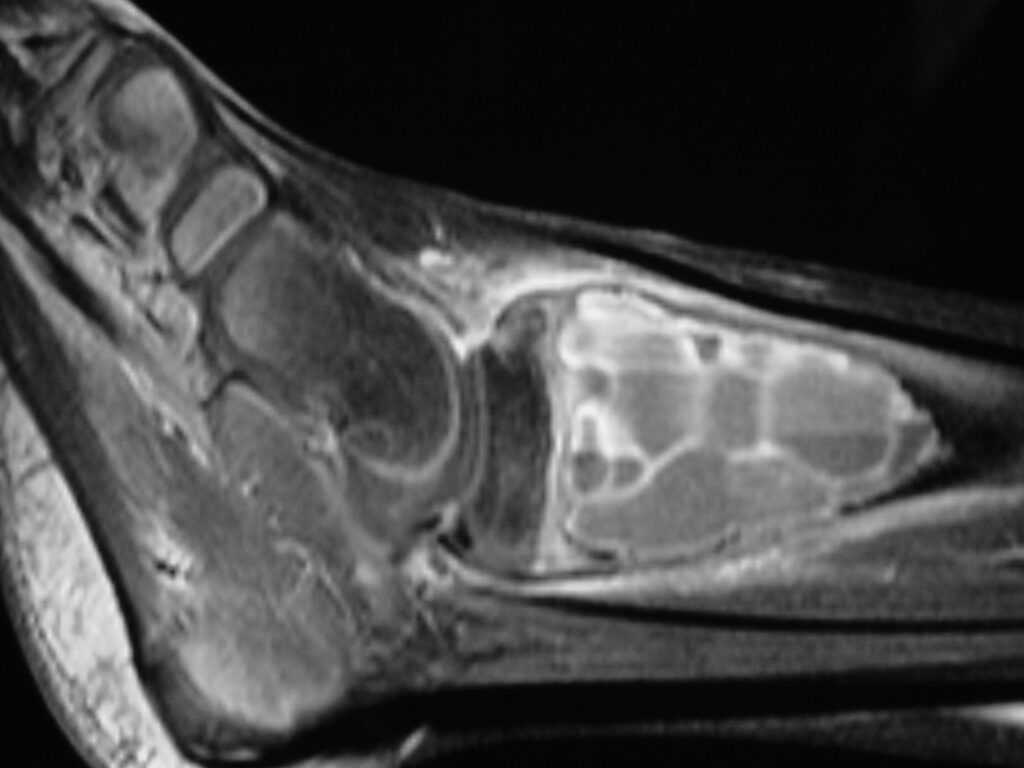

MRI

- Geographic well circumscribed

- High signal on T2 weighted MRI images

- Fluid/Fluid level (T2) are highly characteristic

Fig 2 a-e. MRI of an ABC of Distal Tibia: Fig 2 a-c: geographic cystic expansile lesion with fluid-fluid levels. The fluid-fluid levels are caused by bleeding into the cavities. The blood collects and the degredation products settle to the gravity dependent areas of the cavities. This shows up as fluid-fluid levels on the MRI. Fig 2 d,e: This is a gadolinium enhanced MRI of the ABC of the distal tibia. There is peripheral and septal enhancement indication cyst formation. The contrast outlines the cystic cavities but does not enter into the center

Fig 2b: Sagittal T2 weighted MRI of and ABC